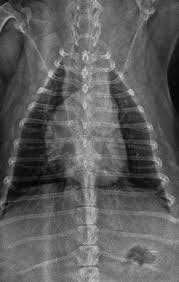

Mujer de 80 años con importante fibrosis pulmonar en rx de tórax el electrocardiograma con importante crecimiento y sibrecarga del ventrículo derecho por.